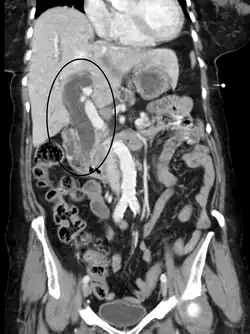

Biliary-tract dilation due to obstruction as seen on CT scan (frontal plane)

Most people presenting with jaundice have various predictable patterns of liver panel abnormalities, though significant variation does exist. The typical liver panel includes blood levels of enzymes found primarily from the liver, such as the aminotransferases (ALT, AST), and alkaline phosphatase (ALP); bilirubin (which causes the jaundice); and protein levels, specifically, total protein and albumin. Other primary lab tests for liver function include gamma glutamyl transpeptidase (GGT) and prothrombin time (PT).[37] No single test can differentiate between various classifications of jaundice. A combination of liver function tests and other physical examination findings is essential to arrive at a diagnosis.[38]

Medical imaging such as ultrasound, CT scan, and HIDA scan are useful for detecting bile-duct blockage.[41]